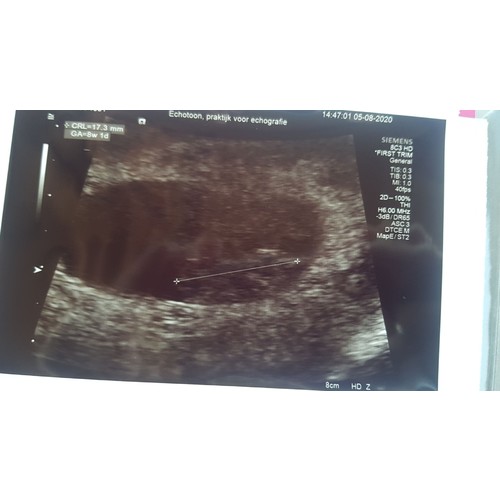

Ik heb PCOS, enige symptoom is teveel eiblaasjes die niet doorrijden. Daardoor geen eisprong. Doormiddel van het medicijn Letrozol lukte dit wel. Iedere 3de tot 7de dag van de cyclus moest ik dat slikken. Vanaf dag 10 echo's om te controleren of er een eicel (of meer) aan het rijpen was. Rond dag 17/18 eisprong, dus rond die dagen maakten we het gezellig. Bij de 5de ronde ben ik zwangergeraakt. Nu ongeveer 7 wk zwanger.

Yes hier.. wij waren al enige tijd bezig om zwanger te worden. Tijdje geleden bij de gynaecoloog te horen gekregen dat ik PCOS heb, dit was duidelijk te zien door de kralenkettingen om mijn eierstokken, menstruatie onregelmatig en vaak hevige menstruatiepijn. Een weekje later na bloedprikken mocht ik starten met Provera (ontrekkingsbloed opwekken) en Letrozol (eisprong). Voordat je start met Provera is het verplicht een zwangerschapstest te doen. Met veel tegenzin gedaan want het is natuurlijk nooit leuk om een negatieve test te zien.. maar die bleek ineens hartstikke positief te zijn! Inmiddels 8 weekjes zwanger.. het kan dus ook echt natuurlijk gaan zonder medicijnen.

Ik heb ook pcos. Dit is mijn 5e zwangerschap. 1e natuurlijk, de 4 daarna met clomid en de laatste nu natuurlijk. We zouden starten met clomid. Helaas 1 kindje overleden in de buik. Ben nu 6+2

Hier ook zwanger met PCOS, ben nu 9+2. Het "grappige" onwel dat ik 9 jaar geleden 10 miskramen heb gehad, allemaal in een traject met clomid en provera steeds en geen succes. Nu toevallig bezig met PCOS symptomen verminderen dmv voeding en binnen een maand zwanger. Het blijft spannend!

Hier ook zwanger, 29 jaar en met diagnose pcos.

Ik ben intussen 8+1. We komen net van de verloskundige. En alles is goed met de kleine uk. 🥰

In februari 2020 kreeg ik de diagnose pcos. Kreeg geen medicatie of dergelijk, alleen dat ik moest afvallen en dat ik na 6 maand terug moest komen.

Op 31 mei een miskraam bij 7+4, zelf wisten we het toen pas 3 dagen. En nu weer zwanger. Binnen 3 weken na de miskraam.

Ik heb ook PCOS.. de klassieke versie.. meer dan 20 eicellen in beide eierstokken gevonden.. in maart dit jaar ontdekt na een miskraam in januari. Proberen al een tijd zwanger te worden en had voorheen altijd een regelmatige cyclus. Sinds de miskraam heb ik tot halverwege juni geen menstruatie gehad en had deze maand een afspraak bij de fertiliteitsarts om te starten met een behandelplan. Wonder boven wonder werd ik halverwege juni ongesteld en inmiddels bijna 7 weken zwanger! Hier kwam ik 2 weken geleden achter. A.s. Maandag de eerste echo! Ben zo benieuwd.. hoop echt dat ik dit kleintje mag voldragen en gezond op de wereld mag zetten😊. De afspraken in het ziekenhuis voor nu maar even afgezegd. Wel houd de verloskundige me goed in de gaten en krijg daarom ook een vroege echo. Kans op een meerling is ook heel groot hierdoor. Spannend!

Hier ook PCOS. Wij zijn nu ruim twee jaar bezig met onze kinderwens. Hebben tussendoor twee miskramen gehad⭐Sinds september 2019 onder controle bij de gynaecoloog. Heb clomid (orale medicatie) gebruikt maar dit hielp niet. Vervolgens overgestapt naar de Gonal-f (injecties). Gelukkig is dit voor mij het wondermiddel🥰 Nu volgens mijn eigen berekeningen rond de 6 weken zwanger. Aankomende dinsdag mijn eerste echo🤞 Super spannend, hopen dat alles goed is met onze kleine Uk❤

Ik heb ook PCOS, heb teveel eiblaasjes in m’n eierstokken en heb een cyste op een eierstok. Ik loop al 4 jaar in het ziekenhuis. Ondertussen wel verhuisd en naar een ander ziekenhuis gegaan en een operatie gehad, mijn rechter eierstok was gedraaid. Begin vorig jaar zwanger geraakt maar na 9 weken was het hartje gestopt met kloppen. Ben begonnen met clomid, werkte niet meer voor mij eind vorig jaar. Toen clomid in combinatie met ouderdomssuiker tabletten geslikt, werkte ook niet. Overgestapt naar Gonal-f, werkte ook niet. Toen Letrozol gaan gebruiken, na de 3e ronde was het raak. Ben inmiddels 9+2 weken zwanger. Wel heel spannend allemaal nog, vooral omdat het de vorige keer niet goed is gegaan. Heb dinsdag m’n 2e echo in het ziekenhuis.